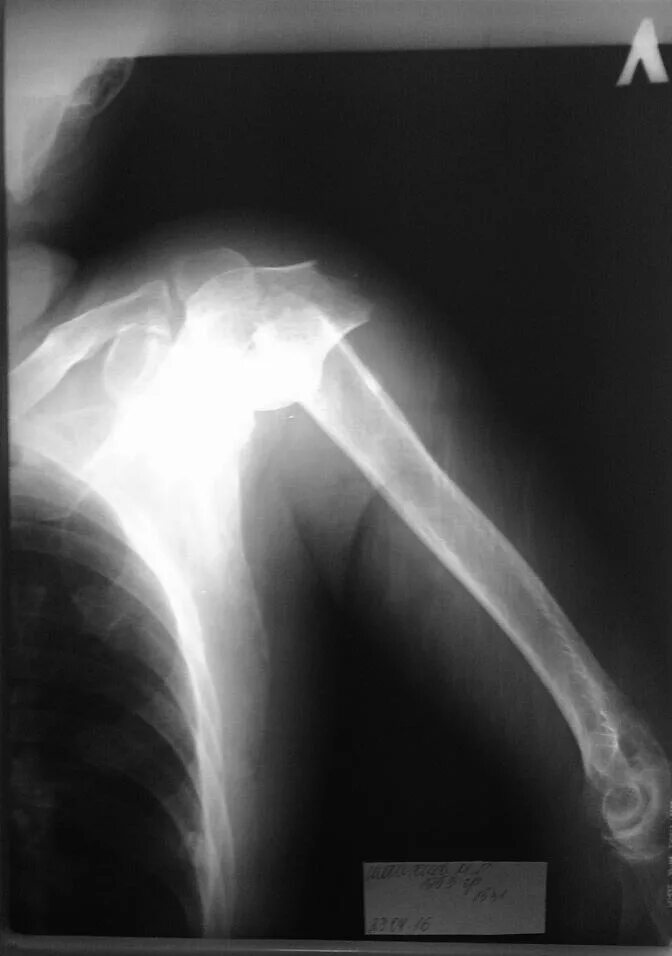

Перелом шейки плеча у пожилых